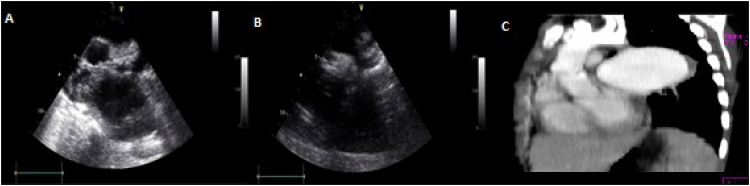

Case description: Two male patients aged 13 and 9 years old were admitted. The first due to a fever for 2 months, which started after dental cleaning, and the second due to high blood pressure, both patients with asthenia and weight loss. In the first case, the transthoracic echocardiogram showed aortic coarctation, and the transesophageal echocardiogram showed the presence of vegetations in the post-coarctation area, without pseudoaneurysms, with blood culture positive for Streptococcus mitis. This patient was treated for six weeks with crystalline penicillin, resolving the infection without complications. The second case was assessed for high blood pressure with a history of fever, and was treated with antibiotics. When performing a transthoracic echocardiogram, aortic coarctation was observed with a saccular image classified as a pseudoaneurysm by angiography and tomography. Blood culture was negative, and the patient developed an episode of hematemesis whose initial etiology could not be determined. Before surgical repair, he had a second episode of copious hematemesis with hypovolemic shock and death.